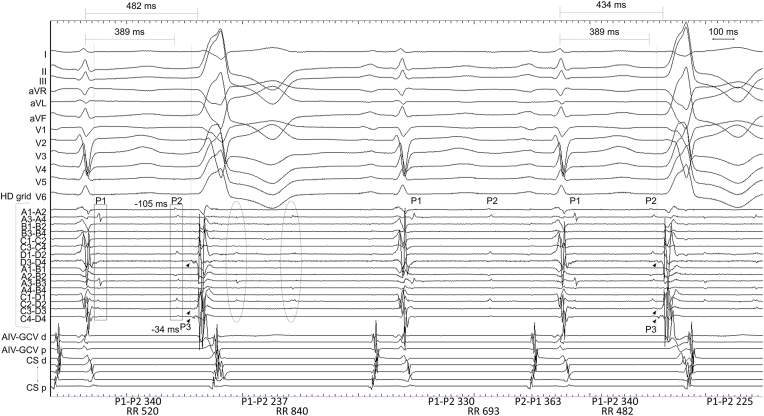

We described a premature ventricular contraction arising from the left coronary sinus cusp, in which we discussed about the interpretations of the signals recorded there. Our case provided further insights into the interpretation of signals recorded at the coronary sinus cusp during premature ventricular contraction ablation.